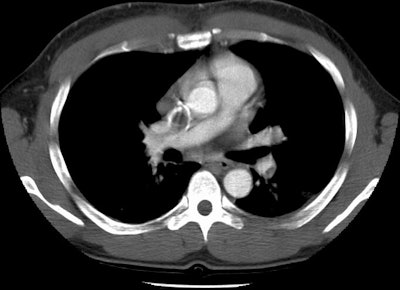

Pulmonary emboli in a lymphoma patient with SVC thrombosis

This case nicely demonstrates clot in both the superior vena cava and the left lower lobe segmental pulmonary arteries. There is also a small clot in a left upper lobe segmental vessel.